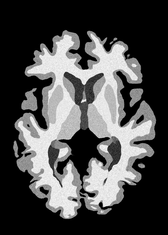

4.2 Registration to a 100 micron ex-vivo brain MRI volume

To showcase the efficacy of our method on real large scale images, we register a 250 in-vivo MRI image (Lüsebrink et al., 2017) to a 100 ex-vivo FLASH human brain volume (Edlow et al., 2019). This represents an inverse problem with more than 11.2B optimizable parameters (compared to 20M for clinical datasets), or 44.8GB of GPU memory. The entire problem does not fit on most GPUs, necessitating distributed multimodal registration. We optimize a composite transform - affine followed by a diffeomorphic mapping; details can be found in Section E.1. Multimodal deformable registration took 58 seconds on 8 NVIDIA A6000 GPUs, which is unprecedented at this resolution. Fig. 6 shows qualitative results, highlighting the ability to register highly detailed structures such as cerebellar white matter; these structures are not visible at macroscopic scales. The resultant advantages of performing registration at this scale can allow researchers to characterize the neuroanatomy at microscopic resolutions and allow morphometric analysis of cortical layers and subcortical nuclei among other structures.